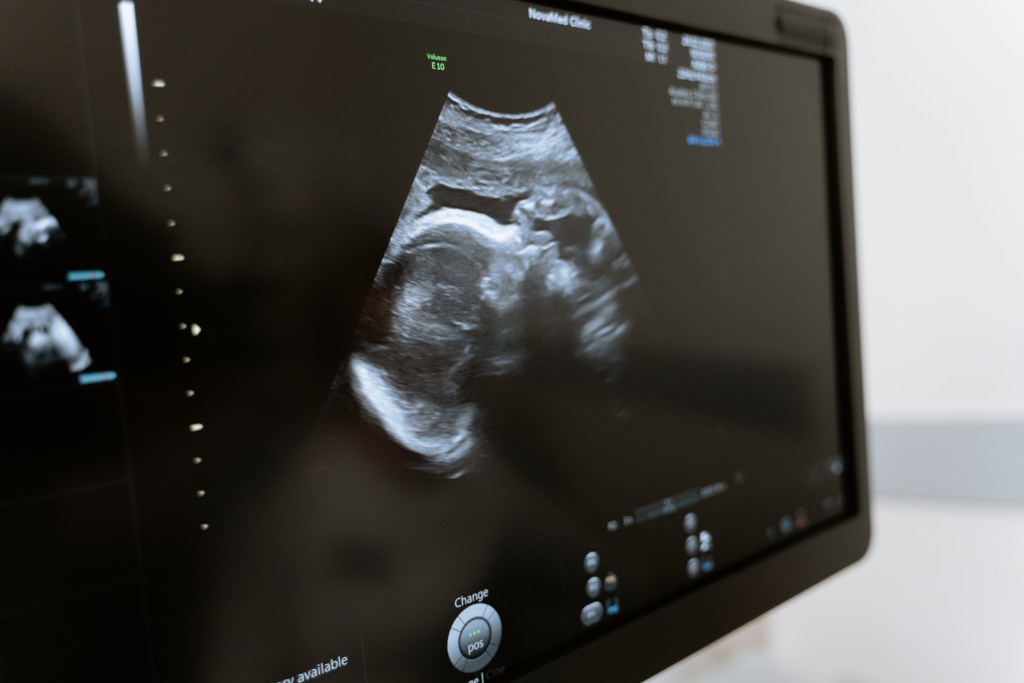

Por fortuna, se cuenta con avanzados medios para el diagnóstico prenatal que hacen posible detectar si el bebé presenta algún tipo de alteración genética. Las ecografías permiten un completo examen físico del feto y detectan de un modo preciso malformaciones congénitas como labio leporino, anencefalia, defectos en los cierres de la columna, alteraciones en los riñones y posibles afecciones cardiacas.

Los exámenes para determinar si existe síndrome de Down o alteraciones del sistema nervioso son cada vez más precisos. Las estadísticas indican que este tipo de anomalías se encuentran en tres de cada 2.000 bebés. Esos datos no nos quitan el miedo, pero la amniocentesis y el llamado análisis prenatal no invasivo, sí. Ahora bien, es el médico quien aconseja hacerse o no este tipo de pruebas teniendo en cuenta los antecedentes familiares, la edad de la madre y el resultado de diferentes pruebas médicas. En última instancia es la madre quien decide si someterse o no a la amniocentesis.